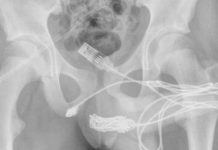

La donovanosis o granuloma inguinal es una rara enfermedad de transmisión sexual, causada por la bacteria “klebsiella granulomatis”, que, según explicaciones anteriores del farmacéutico Shamir Patel, “infecta la piel alrededor de los genitales, la ingle o el área anal y causa lesiones y la desintegración de la piel a medida que la carne se consume de manera efectiva”.

Para diagnosticar la donovanosis, un médico debe raspar la base de sus úlceras para obtener una muestra del tejido, teñir la muestra de tejido con tinción de Giemsa o Wright y luego observar la muestra bajo un microscopio, buscando los llamados cuerpos de Donovan.

Los cuerpos de Donovan son la presencia de numerosas bacterias dentro de los macrófagos., los cuales son células que existen en todo el cuerpo y mastican a los invasores como bacterias, de forma similar a como Pac Man engulle puntos y frutas. Entonces, los cuerpos de Donovan son una señal de que tiene donovanosis y debe comenzar el tratamiento con antibióticos de inmediato.